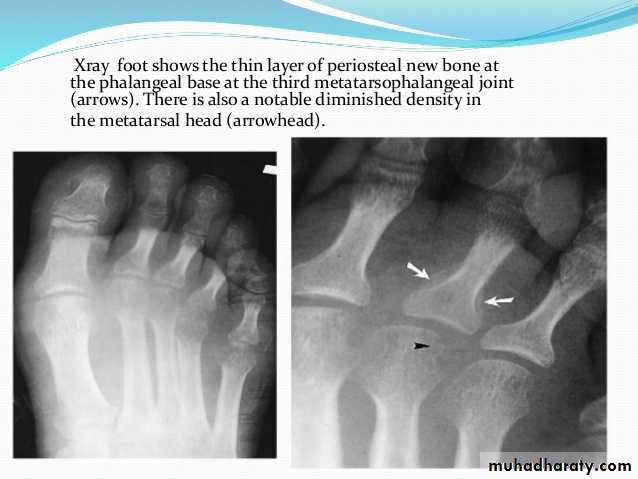

In chronic or recurrent disease, X-rays show joint space narrowing and proliferative erosions.Another characteristic feature is periostitis, especially of metatarsals, phalanges and pelvis, and large, ‘fluffy’ calcaneal spurs.

In contrast to AS, radiographic sacroiliitis is often asymmetrical and sometimes unilateral, and syndesmophytes are predominantly coarse and asymmetrical, often extending beyond the contours of the annulus (‘nonmarginal’)

X-ray changes in the peripheral joints and spine are identical to those in psoriatic arthritis.